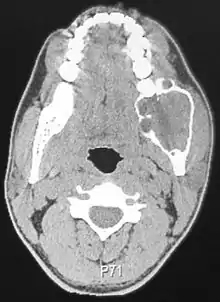

| Ameloblastoma of the mandible | |

Ameloblastomas can be found both in the maxilla and mandible. Although, 80% are situated in the mandible with the posterior ramus area being the most frequent site.[9] The neoplasms are often associated with the presence of unerupted teeth, displacement of adjacent teeth and resorption of roots.[10]

Radiographically, the tumour area appears as a rounded and well-defined lucency in the bone with varying size and features. Numerous cyst-like radiolucent areas can be seen in larger tumours (multi-locular) giving a characteristic "soap bubble" appearance. A single radiolucent area can be seen in smaller tumours (unilocular).[8] The radiodensity of an ameloblastoma is about 30 Hounsfield units, which is about the same as keratocystic odontogenic tumours. However, ameloblastomas show more bone expansion and seldom show high density areas.[14]

Lingual plate expansion is helpful in diagnosing ameloblastoma as cysts rarely do this. Resorption of roots of involved teeth can be seen in some cases, but is not unique to ameloblastoma.[10]